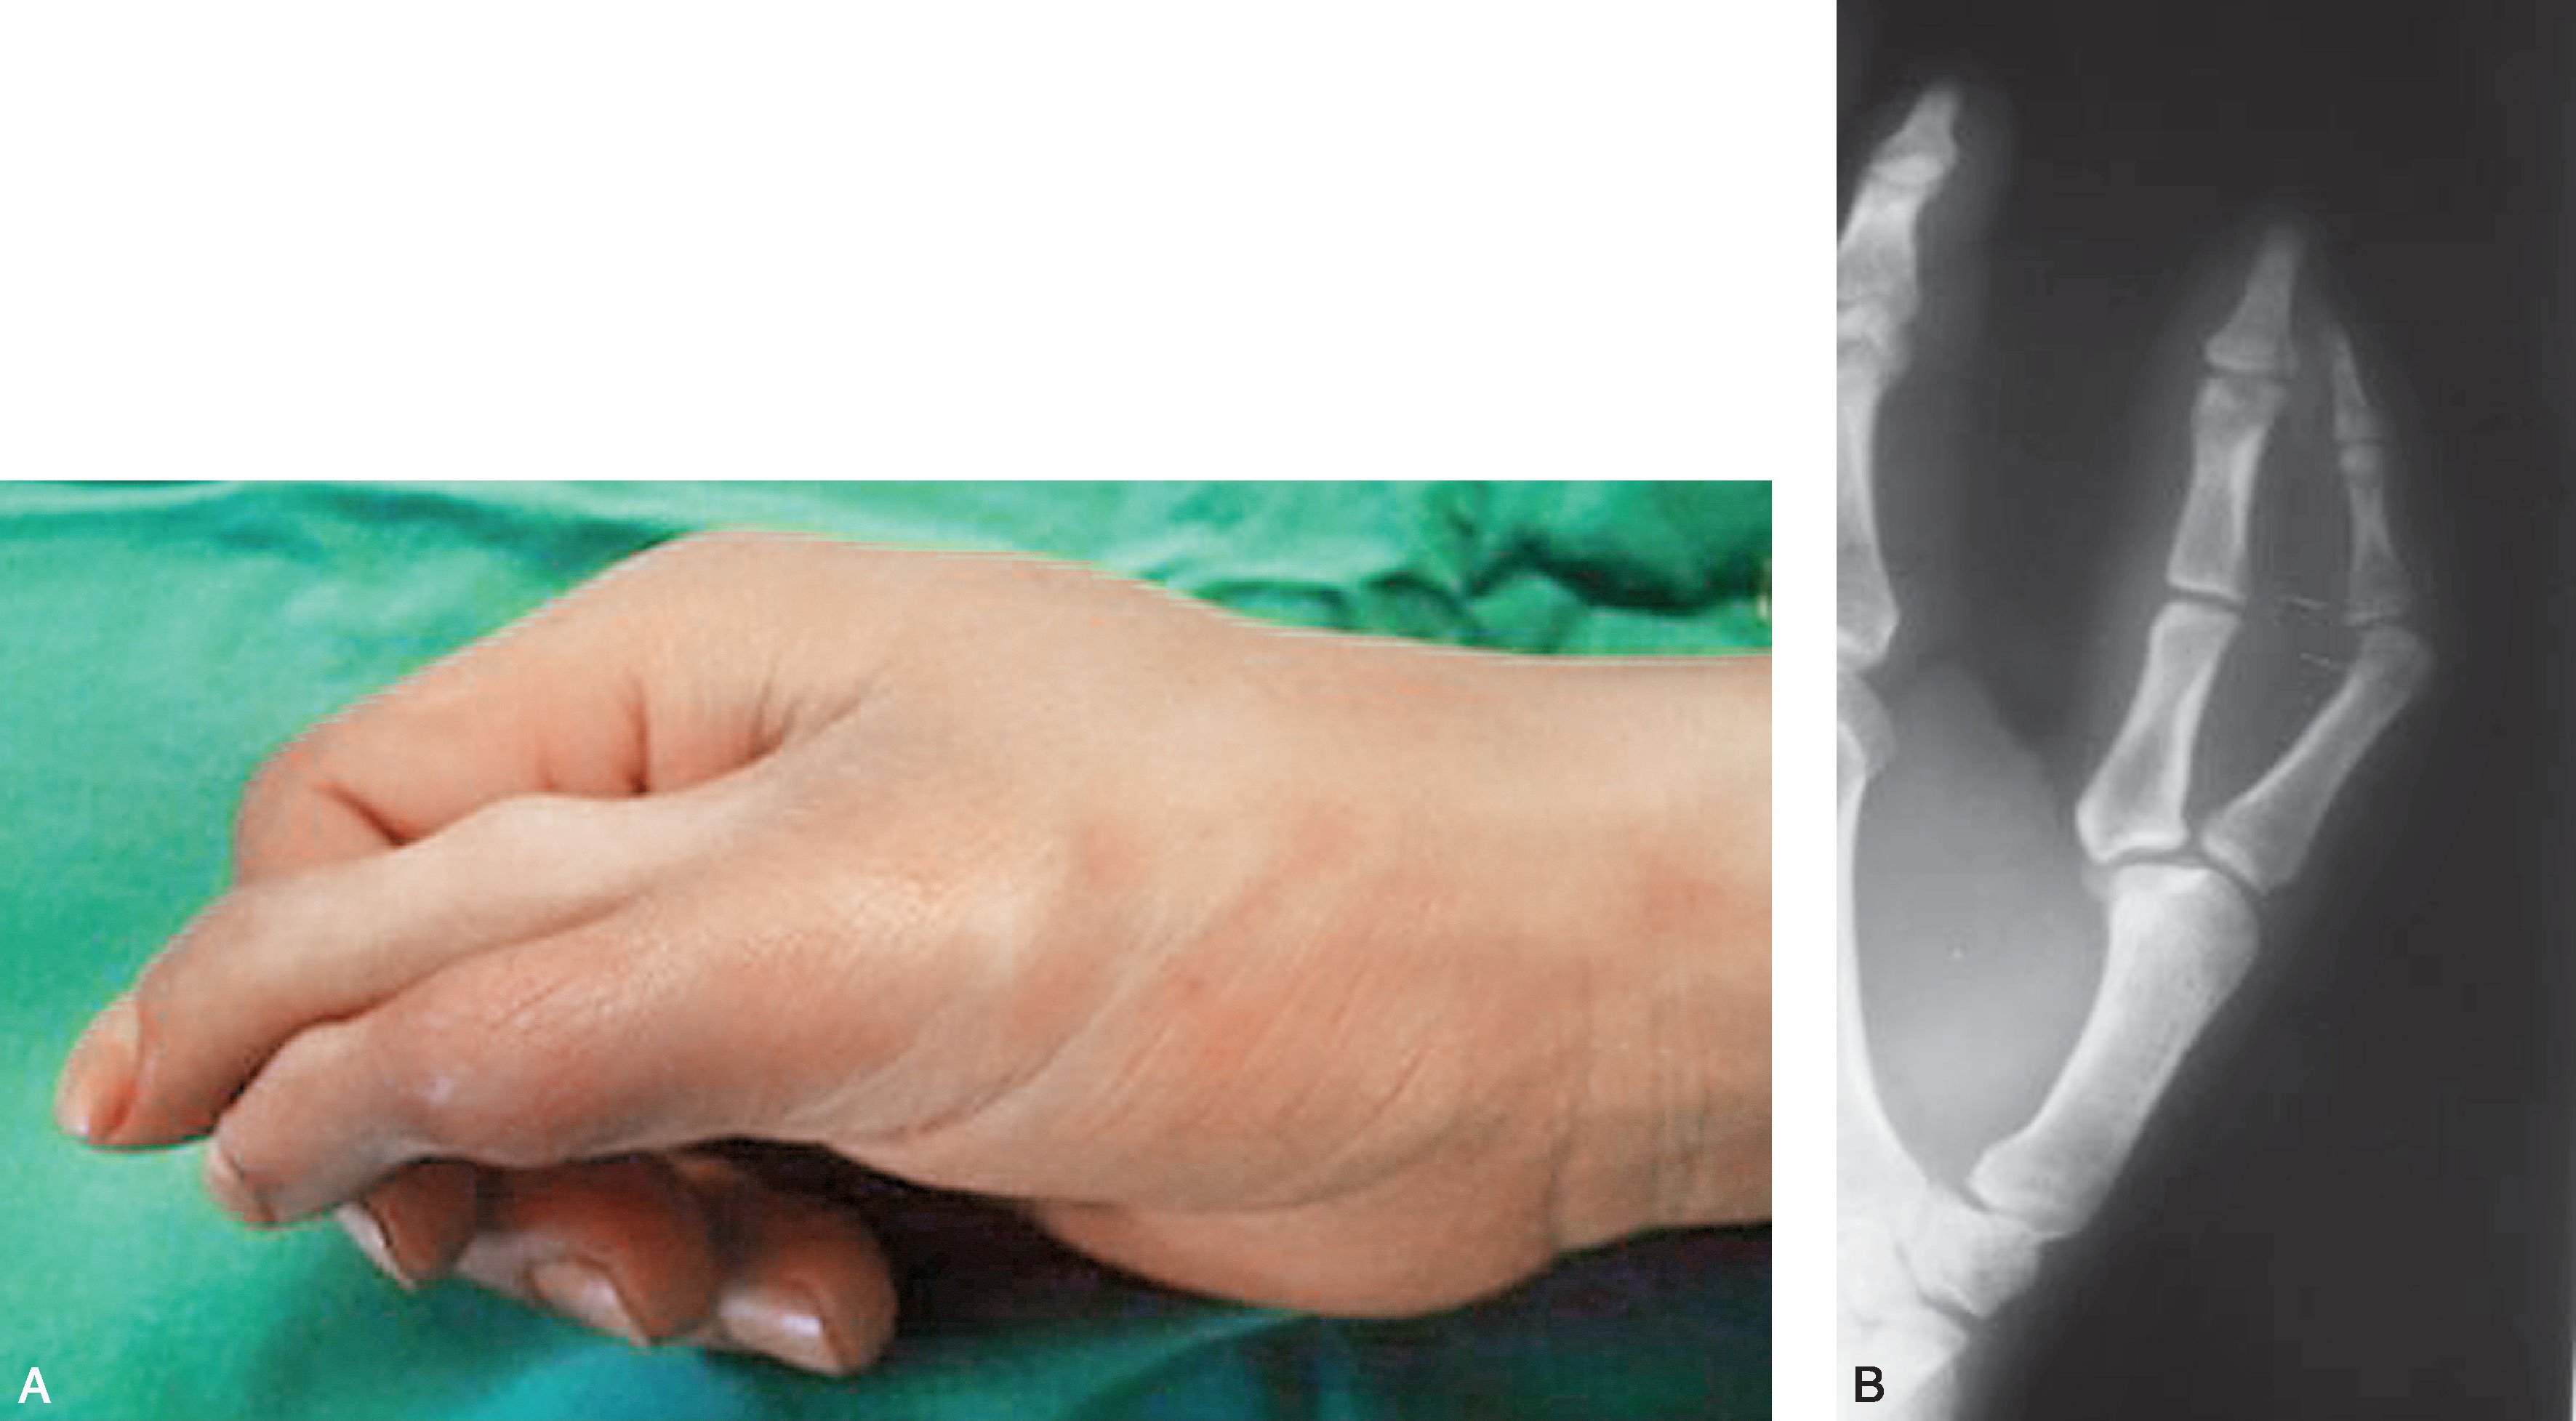

1.Ⅰ型 末节指骨未完全分裂,近节指骨正常或不正常,共用一个骨骺,并与近节指骨远端形成关节(图2-1-1~图2-1-4)。

图2-1-1 Ⅰ型病例1

A.主拇指与次拇指外形差异较大,各自有独立的指甲,远节尺偏(左侧);B.X 线片显示,虽然指骨远端分开,但基底共用一个骨骺,重建时需手术切除部分桡侧骨骺板,远节指骨尺偏需行近节指骨远端桡侧闭合楔形截骨,以纠正远节手指的尺偏畸形